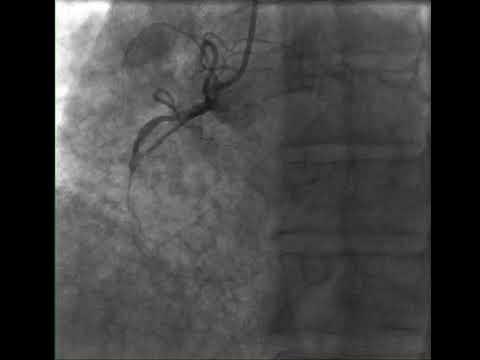

MINOCA – Myocardial Infarction with Nonobstructive Coronary Arteries

MINOCA – Myocardial Infarction with Non-obstructive Coronary Arteries

Myocardial infarction with non-obstructive coronary arteries (MINOCA)

Myocardial Infarction With Non Obstructive Coronary Arteries | MINOCA

ST Elevation Myocardial Infarction in Angiographically Non-Obstructed Coronary Arteries